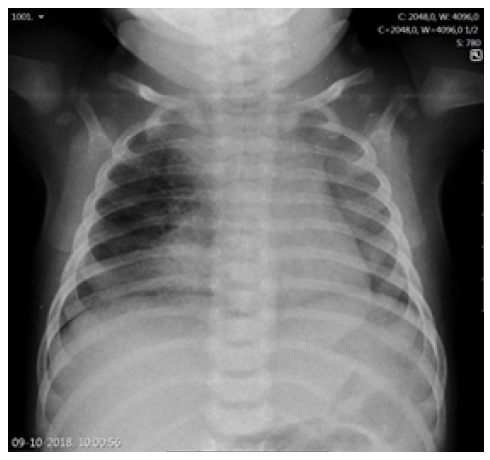

The duration of fever, young age, and subsequent immunization status (the girl had not yet received the two-month vaccines required by the national immunization program) prompted etiologic study, and a complete blood count revealed leukocytosis with neutrophilia (white blood cell count 29,300/uL, neutrophils 21,000/uL, lymphocytes 4,900/uL), hemoglobin of 10.1g/dL, and platelet count of 590,000/uL. C-reactive protein (CRP) was 47.2mg/L and procalcitonin (PCT) was 0.29 ng/mL. Altered coagulation study (international normalized ratio [INR] 1.45 and prothrombin time 16.7 seconds) were reversed after a single vitamin K administration. Serum electrolytes, renal function, and liver enzymes were normal. Chest radiograph showed a right apex and right perihilar infiltrate (Figure 1). Lumbar puncture was performed after clinical deterioration, and cerebrospinal fluid (CSF) analysis was normal (5/uL cells, 1/uL erythrocytes, glucose 54 mg/dL, proteins 0.42g/L).